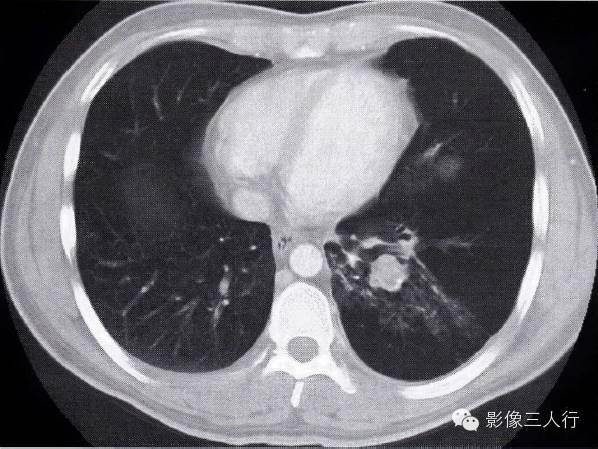

肺结核合并肺癌的CT表现及鉴别诊断

图2-94肺结核合并肺癌

左肺下叶肺结核,斑状影,条索状影,内有结节影,肺穿刺为腺癌 在肺不张时见支气管阻塞,肺门区出现肿块而且肺门区出现支气管腔内外融合成一体的肿块,腔内与腔外部分呈一致性强化。肺不张内无明显空洞及扩张的支气管影。